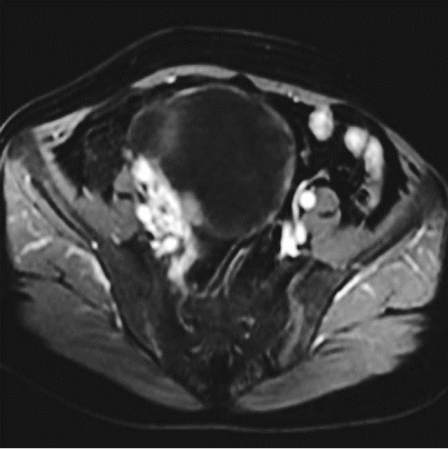

1.影像学检查 ①超声检查:可根据肿块的囊性或实性、囊内有无乳头等判断肿块性质,诊断符合率>90%。彩色多普勒超声扫描可测定肿块血流变化,有助于诊断。②磁共振、CT、PET检查:磁共振可较好判断肿块性质及其与周围器官的关系,有利于病灶定位及病灶与相邻结构关系的确定;CT可判断周围侵犯、淋巴结转移及远处转移情况;PET或PET-CT一般不推荐为初次诊断。

卵巢畸胎瘤腹中X线 摄片卵巢恶性肿瘤MR检查

盆腔右侧见一大小为1.7×1.5cm不均匀 盆腔右侧子宫前方不规划囊实性混杂性号影,有 高密度钙化影,边界尚清 分隔及软组织成份,增强扫描实性结节呈中强度改变